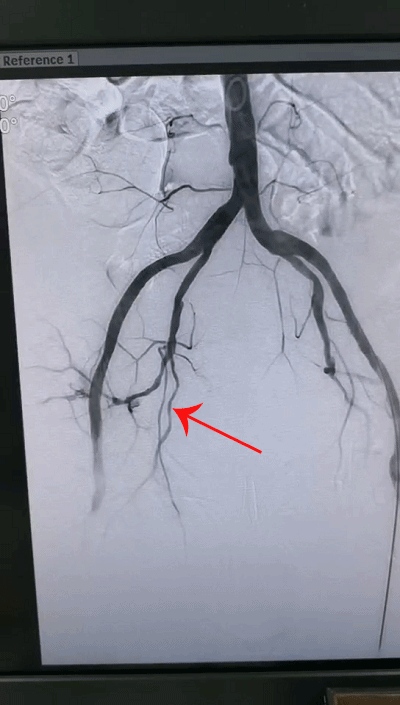

也正是在此时,短短数分钟之内,老人的血压迅速下降,心率不断加快,近乎休克,如不尽快处理,随时可能丧命,情况十分危急。深圳市中医院介入科紧急为老人实施了腹主动脉、髂动脉造影,迅速确定了出血位置,进行右侧髂内动脉超选择性栓塞治疗:通过微创介入技术[c1] ,使用微导管从大腿处进入动脉血管,在达到破损处后精准填入明胶海绵[c2] 与弹簧圈,栓塞封闭破损血管而成功阻止出血!手术之后,老人的血压和心率逐渐恢复正常,生命体征基本平稳。

栓塞后成功阻止出血